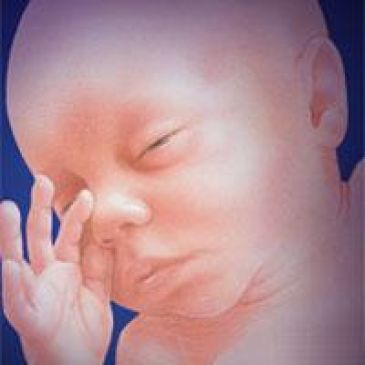

23-25-й тиждень. Плід як і раніше багато рухається: він робить від 20 до 60 рухів за півгодини, звичайно, по-різному в різний час дня. Тепер у нього бувають фази сну і неспання, він починає реагувати на зовнішні звуки. Його особа стає тоншою: з'являються брови, виразніше вимальовується ніс, вуха стають більше, з'являється шия. Він часто смокче палець і іноді гикає

26-27-й тиждень. Легкі досягають значного розвитку, але остаточно будуть готові дихати тільки в кінці восьмого місяця. У разі передчасних пологів дитина може вижити. Його зріст тепер 37 см, вага - 1 кг

28-29-й тиждень . Дихальні рухи плода стають все менш безладними. Очі повністю відкриті. Функціонують шлунок і кишечник. Формування нирок майже закінчено, але вони будуть повністю готові до роботи тільки після народження. Вуха вже на своєму місці, плід реагує на звуки